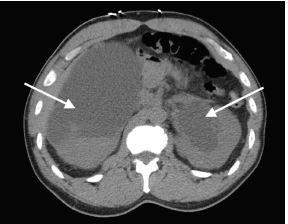

We report the case of a 57-year-old man who presented to the ED with difficulty voiding. A urinary catheter was placed. The patient had severe post-obstructive diuresis. He developed hematuria and became hypotensive. After aggressive resuscitation, including blood products, the patient required operative intervention for hemorrhage control.

我们报告一例57岁男性患者,因排尿困难就诊于急诊科。置入了导尿管。该患者出现严重的梗阻后利尿。他出现血尿并发生低血压。在积极复苏,包括输注血液制品后,患者仍需要手术干预以控制出血。